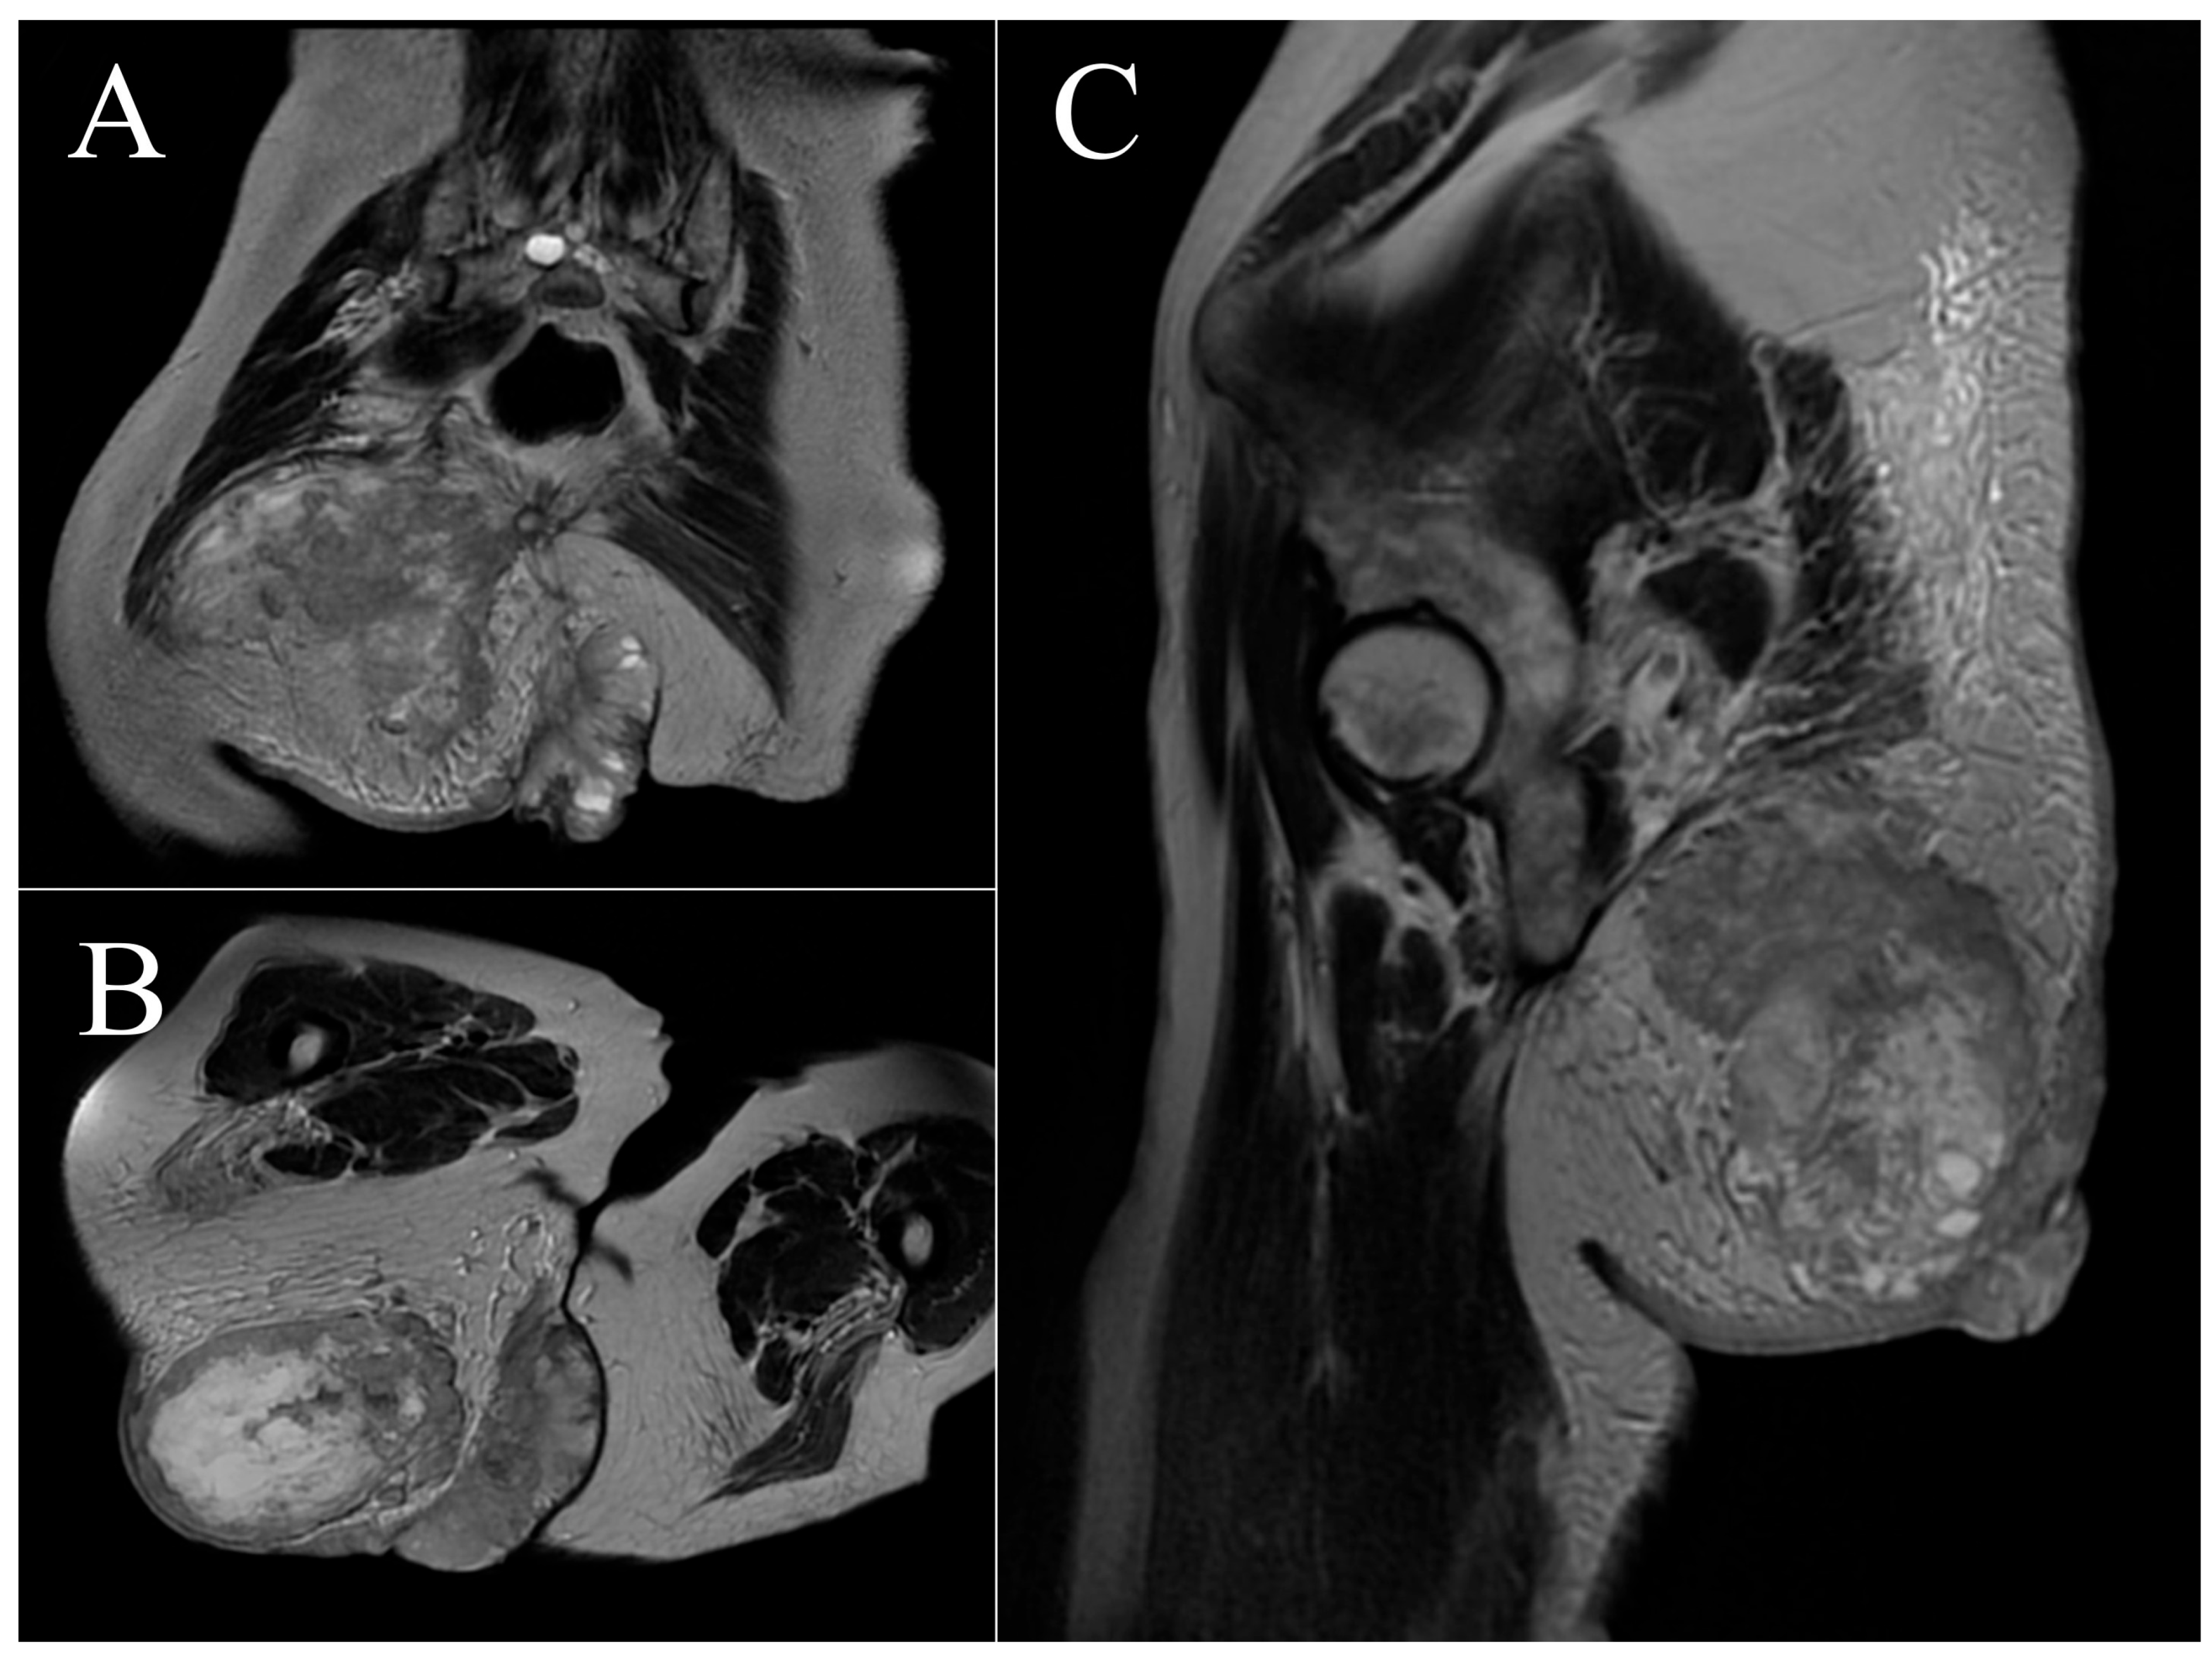

2.2. Case 2

3.2. Case 2